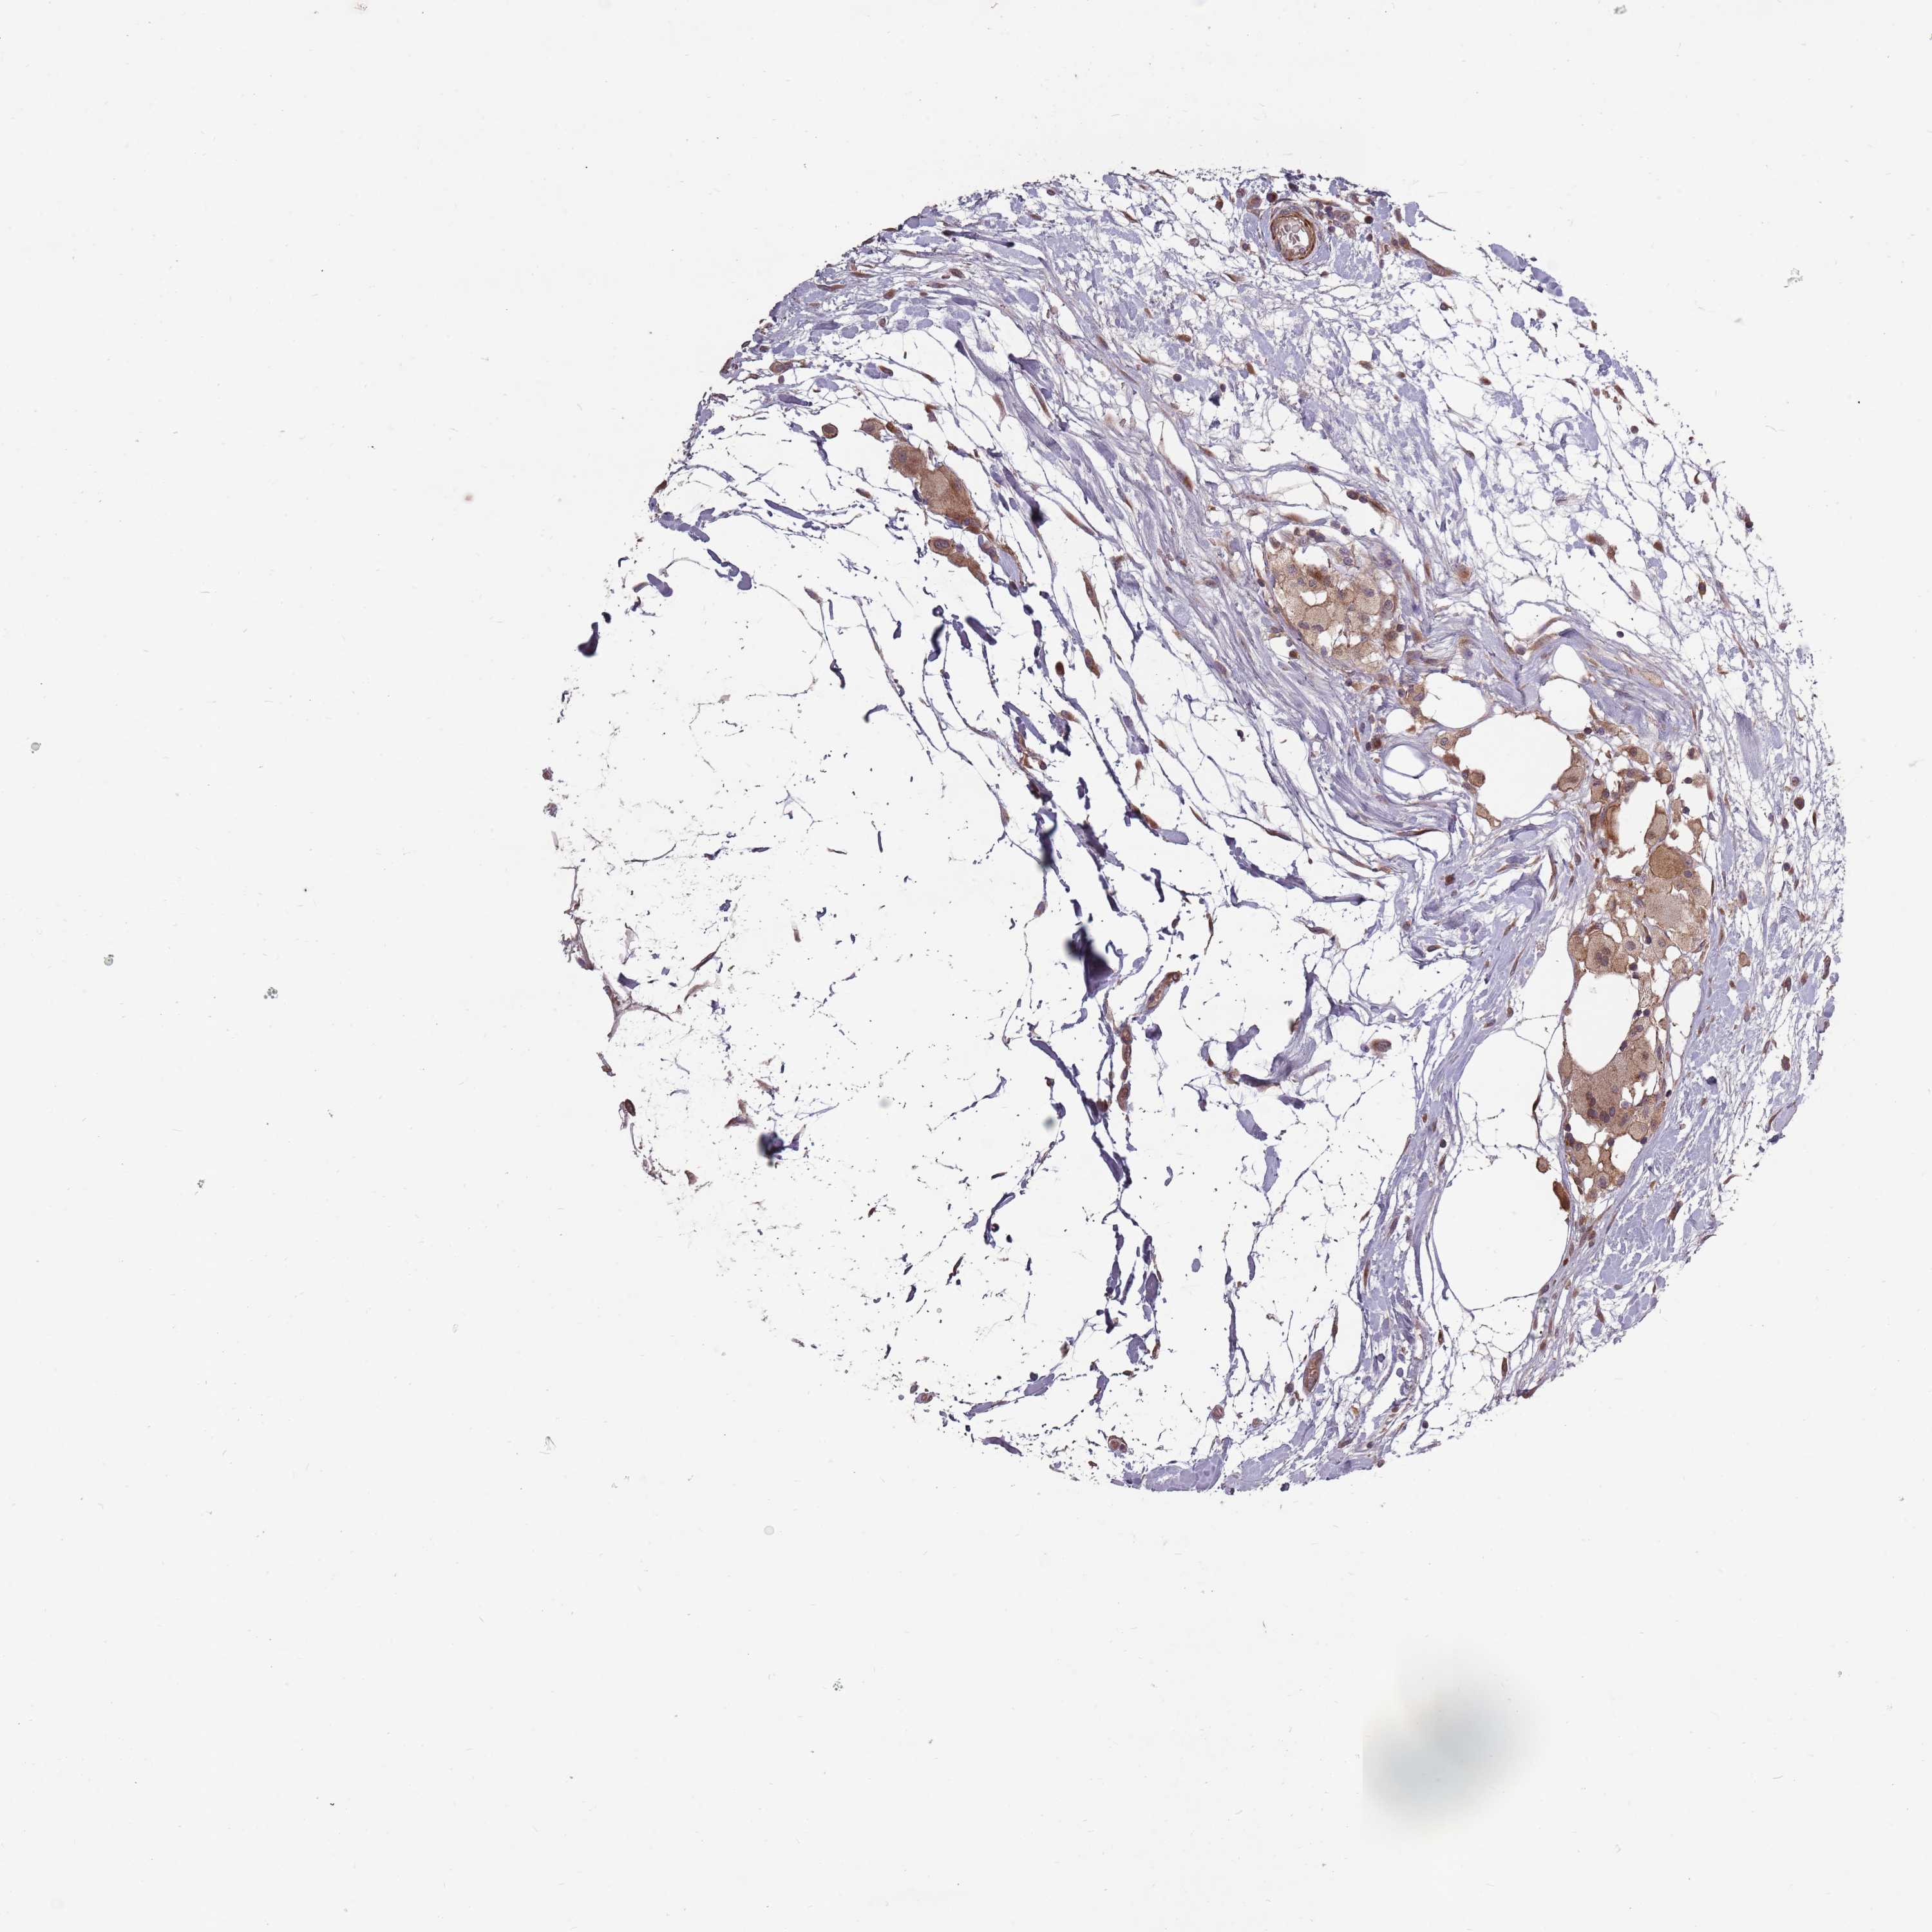

CANCER BREAST CANCER Show tissue menu

BRCA TCGA BRCA VALIDATION PROTEIN EXPRESSION